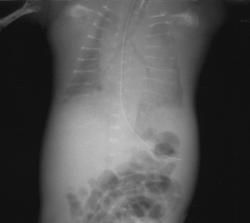

Однако далеко не во всех случаях гипофосфатазии у плода ультразвуковое исследование скелета демонстрирует снижение эхогенности костей. J. Witts и соавт. описывают клиническое наблюдение, при котором в 17 нед беременности у плода отмечался незначительный подкожный отек и небольшое укорочение конечностей при их нормальной оссификации. Кариотип плода был нормальным, и беременность пролонгировали. В 31 нед укорочение костей стало выраженным, присоединилось многоводие. Для исключения ахондроплазии был сделан анализ на мутацию, характерную для этого заболевания. Ребенок родился в 35 нед и погиб сразу после родов. Только при рентгенологическом исследовании была выявлена сниженная минерализация черепа, платиспондилия позвоночника и истончение ребер, после чего было произведено гистологическое исследование костей и молекулярная диагностика, направленная на выявление мутаций, характерных для гипофосфатазии.

ГИПОФОСФАТАЗИЯ - заболевание костной системы, связанное с недостаточной активностью щелочной фосфатазы (фосфомоно-эстеразы). Описано в 1948 г. Rathbun. До последнего времени в литературе описано более 50 наблюдений данного заболевания. Тип наследования - аутосомно-рецессивный. В патогенезе основную роль играет снижение или отсутствие активности энзимов, обеспечивающих отщепление неорганического фосфата от фосфорорганических соединений. В результате резко нарушаются процессы минерализации органической матрицы кости. Гистологическая структура костей и хрящей весьма сходна с наблюдающейся при обычном рахите - нарушение процессов оссификации, особенно выраженное в метафизах трубчатых костей, чередование участков обызвествленной и хрящевидной ткани. Диафизы обызвествляются удовлетворительно.